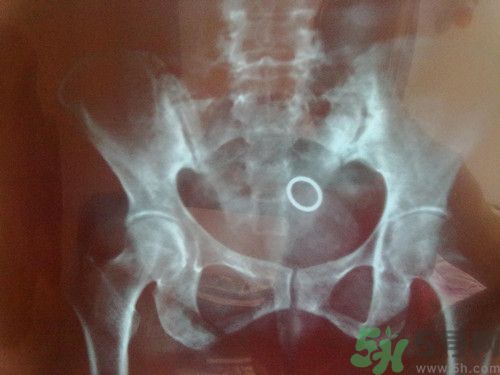

今天微博都被周杰倫患脊柱炎的消息刷爆了,脊柱炎到底是什么病呢?聽(tīng)著好嚴(yán)重的樣子?能不能治好呢?下面我們來(lái)一起看看具體內(nèi)容!

1.強(qiáng)直性脊柱炎。年輕人發(fā)病多,一般不超過(guò)三十歲,男性多于女性。

2.未分化脊柱關(guān)節(jié)病。沒(méi)有得到明確診斷的脊柱炎,也就是沒(méi)有強(qiáng)直性脊柱炎的典型癥狀。

3.增生性脊柱炎。多發(fā)于老年人,屬于代謝性疾病,有竹節(jié)樣變化。